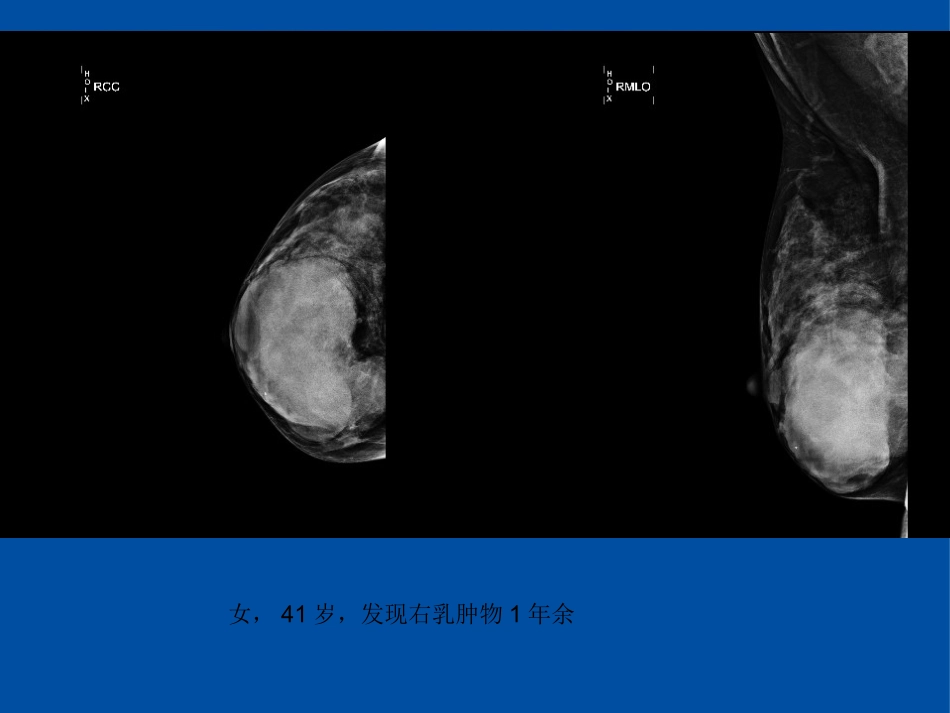

女,41岁,发现右乳肿物1年余女,39岁,发现右侧乳房肿物3月女,50岁,发现左乳肿物2月余。女,21岁,B超发现右乳肿物女,43岁,发现右乳肿物10余年女,43岁,发现右乳肿物乳腺叶状肿瘤影像表现临床•由间质细胞和上皮两种成分共同组成的肿瘤。•少见,约占乳腺肿瘤的0.3%~1%,约占乳腺纤维上皮肿瘤的2%~3%•中年妇女居多,平均45岁左右•最常见临床表现:无痛性肿块•肿瘤增长缓慢,病程较长,也可短期内突然增大病理•根据肿瘤间质成分的细胞密度、细胞异型性、核分裂象、异源性物质是否存在等,将其分为:良性(I级)、交界性(II级)和恶性(III级)。•大体病理:多较大,常呈分叶状,质地韧,界限清楚,多有完整包膜•小的肿瘤呈实性,大的肿瘤可有囊腔•文献报道肿块内囊变为叶状肿瘤的特点生物学行为•叶状肿瘤的生物学特性与病理类型并不完全吻合:良恶性都易术后复发。•肿瘤复发可能与切除不完全有关•主要发生血行转移,腋窝淋巴结转移者甚少治疗•核心原则是:无论肿瘤是良性还是恶性均需行扩大切除,以保证切缘阴性;对于肿瘤>5cm者可考虑单纯乳房切除术。•首次术式的选择与复发率、死亡率密切相关,术前最好能做出明确的诊断,以便能选择正确的手术方式进行治疗。影像学表现(1)无论良性、交界性还是恶性,均多呈分叶状,但小的肿瘤可为圆形、椭圆形。•分叶的切迹可能与镜下所见分叶状结构间的裂隙有关。(2)无论良性、交界性亦或恶性,边界均清楚,•与肿瘤膨胀性生长,周围腺体受挤压形成假包膜有关。虽然部分交界性及恶性肿瘤在镜下见肿瘤浸润周围组织而边界不清楚,但于影像不易显示,仍表现为边界清楚。(3)钙化少见(4)实性成分密度(或回声或信号)多均匀•在钼靶X线上为等或高密度,在超声上为低回声,在MRI上为T1WI稍低和T2WI稍高信号。•肿瘤是否出现囊变与肿瘤大小有关。<5cm者不易出现囊变;而>5cm者无论良性还是非良性均易出现囊变(5)不易出现腋下淋巴结及远处转移鉴别良性、非良性•形态、边界上无法区分•超声回声是否均匀及血流是否丰富的角度也无统计学差异•部分研究认为肿瘤大小有助于鉴别肿瘤良恶性:肿瘤越大交界性及恶性的可能性越大,术后复发的可能性增加,但没有确定判断良恶性的肿瘤大小的界值女,50岁,发现左乳肿物2月余。--恶性叶状肿瘤女,41岁,发现右乳肿物1年余鉴别诊断纤维腺瘤叶状肿瘤①大小:1-3cm>5cm②形态:圆形、椭圆形分叶状③钙化:常见少见④囊变:少见多见⑤MRI如果能提供支持肿瘤为恶性的功能信息,则更提示叶状肿瘤右乳外上纤维腺瘤女,46岁,发现双侧乳房肿物2年余鉴别诊断•乳腺癌:近绝经期或绝经后期,边缘多不整齐,有毛刺或浸润,皮肤常受累,乳头回缩,影像上密度(或回声或信号)不均匀,周围结构扭曲常,见钙化灶(恶性钙化)发现左乳肿物10余年,进行性增大7月(左乳腺穿刺组织)浸润性癌伴坏死及钙化。女,36岁,(左侧乳腺肿物)交界性叶状肿瘤(肿瘤大小7.7*6*4cm)(右侧乳腺肿物)腺病伴部分导管大汗腺化生。女,54岁,(左乳)浸润性导管癌(Ⅲ级),最大径2.5cm,浸润周围脂肪组织,女,69岁,发现右乳肿物10年余。浸润性癌。小结边界清楚的分叶状,小肿瘤密度(或信号)多均匀,而大的肿瘤常因囊变而密度(或信号)不均匀,密度较高,不易钙化,不易淋巴结转移:应考虑叶状肿瘤可能。